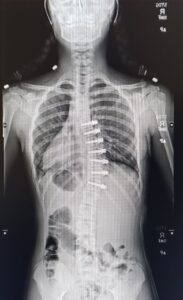

At that point, we knew that surgery was something we needed to look into. My back was giving me a lot of problems and I just wanted it to be fixed. I’d had appointments with a surgeon who did the VBT (Vertebral Body Tethering) surgery before when my spine was holding stable, and we really didn’t think that it was something we would actually have to do. VBT is a newer surgery where a tether is weaved through the spine and pulled taut. It provides full range of motion for the patient once they are fully recovered. I had been trying to avoid the spinal fusion, which doesn’t provide a lot of mobility in the spine and has a long recovery process. The VBT surgery is much less invasive than the fusion. But, VBT has a very limited window of opportunity for the surgery to take place in. At that point, I was almost out of that window. My family had a very difficult decision to make, and we had to do it fast.

Two weeks after the June 2020 appointment, I went back to the clinic to be fit for a new brace. My old one was breaking and not fitting as properly as it should. We talked to many different people during that appointment and asked them all what they would suggest we do. We ultimately decided VBT surgery was in our best interest. It was the best option for me as a dancer, but that didn’t make it any less scary. My surgeon and her team helped push me forward so that I could get my surgery before it was too late. On August 13, 2020, just two weeks after we made the decision, I had VBT surgery. Hospital stays are never fun, but that being said, I think that I was very lucky with having a short hospital stay and recovery time. I was blessed with a great pain management team that helped me feel good throughout my stay. The first week or so was certainly the hardest (although I don’t remember much from the hospital) but they let me go home after about a week, and by the end of that time I was up and walking, climbing stairs, and feeling pretty good. My strength that comes from dancing was very beneficial in the hospital and helped me leave faster than other patients. I was then able to continue the recovery process at home.

At just six weeks post-op, I was told by my surgeon that I could go back to dance and start off with some really light barre work! I chose not to go back right away, just to give my body more time to heal, (and with the pandemic not a lot was going on anyway) so I decided not to push it even though I felt just like normal again. At twelve weeks post-op I was officially recovered and was told I could go back to regular activities.

I had surgery August 13, 2020, and I have had no pain since surgery. I actually feel much better than before surgery because before surgery my back hurt. Now the pain is non-existent. This is different for everyone, but from my understanding, most VBT patients go on to live very normal lives even shortly after surgery! Looking back on it now, I realize that even though it was hard, we made the right decision. My scars are hardly even noticeable! I only have five scars and they are super tiny.